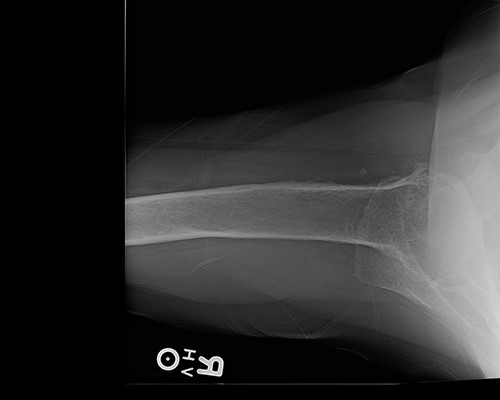

Operative findings revealed an essentially absent subscapularis, supraspinatus, and infraspinatus. The tendon of long head of bicep was hypertrophied and flattened, trying to act as the rotator cuff. Tenotomy was performed at the level of the superior aspect of the pectoralis insertion on the humeral shaft. The humeral head articular surface was hardened with notable black pigmentation around the periphery (Fig. 3). The glenoid articular surface was essentially denuded of articular surface cartilage.

Annular ochronotic pigmentation of right humeral head articular surface.